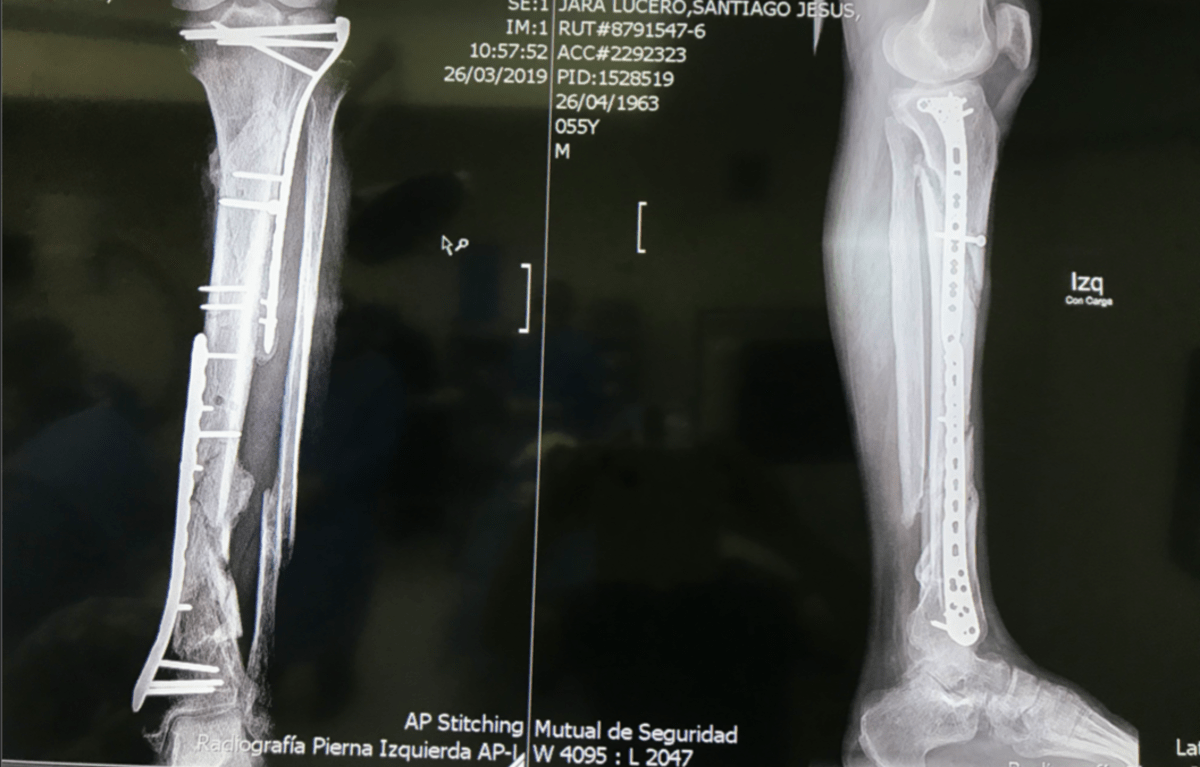

We will operate as first assist with the chief of trauma as well as other orthopaedic faculty and see patients in clinic. In addition to acute trauma, residents will also operate on complex trauma and subspecialty cases including chronic nonunions and malunions, limb deformity and salvage.

During our two weeks in Santiago, Chile we interacted with residents, fellows and attendings at various stages of training and practice. We reviewed complex Orthopaedic trauma cases and strategies in fixation and operated in a variety of settings. Although we were able to share our "American" perspective I think it was myself and my co-resident that I traveled with that were impacted the most. We were able to experience the extremes of chilean healthcare-from patients referred from the public hospitals with chronic nonunions who had been waiting and saving for surgery for years as well as the other end of the spectrum in the private hospital with resources beyond what we have in the US.